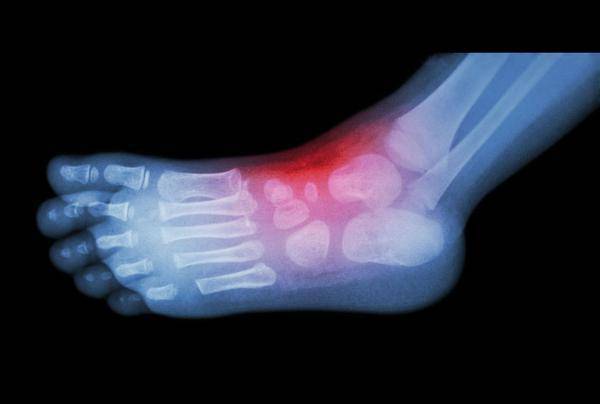

痛風、尿酸高很可怕,多吃這2種蔬菜,就能輕鬆把尿酸排出體外, 痛風不再打擾了,很多中老年人後悔看晚了

提起痛風 ,許多中老年人都深受其害,是由於人體內的尿酸含量過高所引起的。

而尿酸的升高通常與一種叫做嘌呤 的物質有關,當嘌呤代謝發生紊亂的時候,血液中的尿酸就會增多,引起一種代謝性的疾病,當尿酸值升高到一定程度時就容易引起痛風的發生。

而嘌呤主要來自飲食,但現在有更多的人在生活飲食上都不重視,導致痛風成為常見疾病。其實在生活當中有兩種蔬菜屬於是痛風的剋星,如果常常吃可以使尿酸慢慢的降下來,這兩種蔬菜是什麼呢?